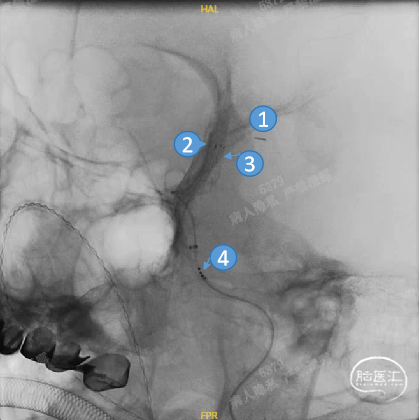

Headway™ 27 156cm微导管内输送FRED 4012血流导向密网支架,系统远端精准定位于预计着陆区远端,回撤微导管原位释放支架,头端即刻打开且锚定牢固后,继续原位释放支架。

正位

①输送导丝头端

②支架远端扩口显影点

③工作区螺旋显影丝

④支架近端扩口显影点

平衡释放支架中段,过弯时确保系统头端处于血管中央,观察到支架自膨打开后,轻推支架以保证支架贴壁。确定近端着陆点处于血管平直区且贴壁良好后,平衡释放支架末端并解脱。